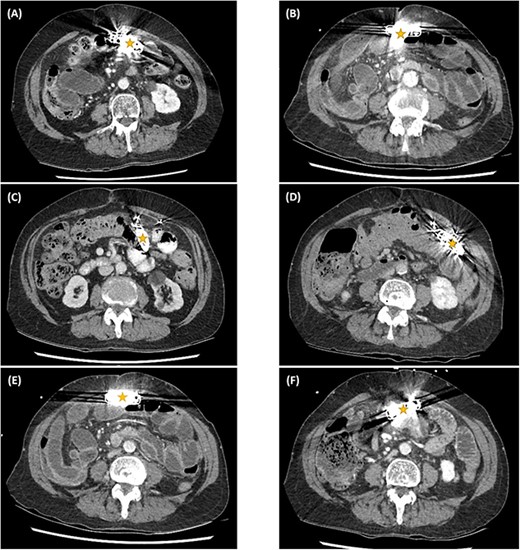

The abdominal computed tomography (CT) studies on all three recent admissions were consistent with SBO. The transition point was consistently seen in the right iliac fossa; with small bowel loops distended proximally with air-fluid levels and faecalised contents; and small bowel loops collapsed distally to the ileocaecal valve (Fig. 1A). There were no signs of bowel ischaemia or perforation. However, the preperitoneal ICD appeared to have migrated into the peritoneal cavity (Fig. 1B). On review of the serial abdominal CT studies over the past two years, the ICD was in a different intraperitoneal location each time (Fig. 2). The recurrent episodes of SBOs were thus believed to be related to the ICD, due to either intraperitoneal migration of the device or formation of adhesions from its placement, given the coinciding timeline.

Serial computed tomography studies from the six episodes of SBOs showing the abdominal ICD device (star) in a different intraperitoneal location each time — in March (A), April (B), and November (C) of 2019; November (D) and December (E) of 2020; and January (F) of 2021.